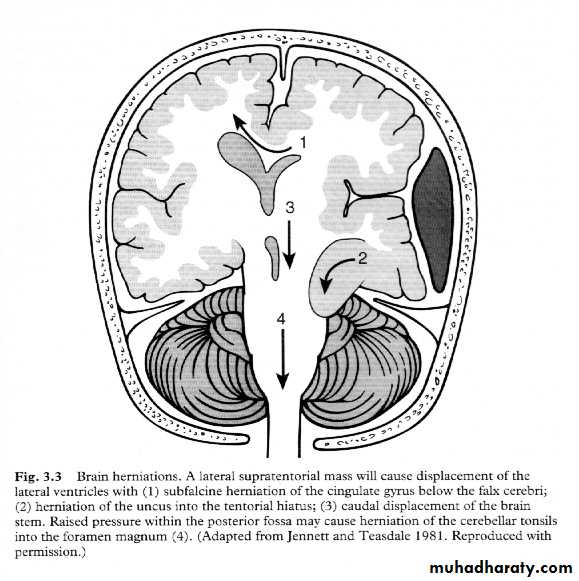

7. Cerebral Herniation

a. Subfalcine Herniationb. Uncal Herniation

c. Tentorial Herniation

d. Tonsillar Herniation

a. Transtentorial Herniation

b. Foramen magnum herniation

c. Subfalcine Herniation